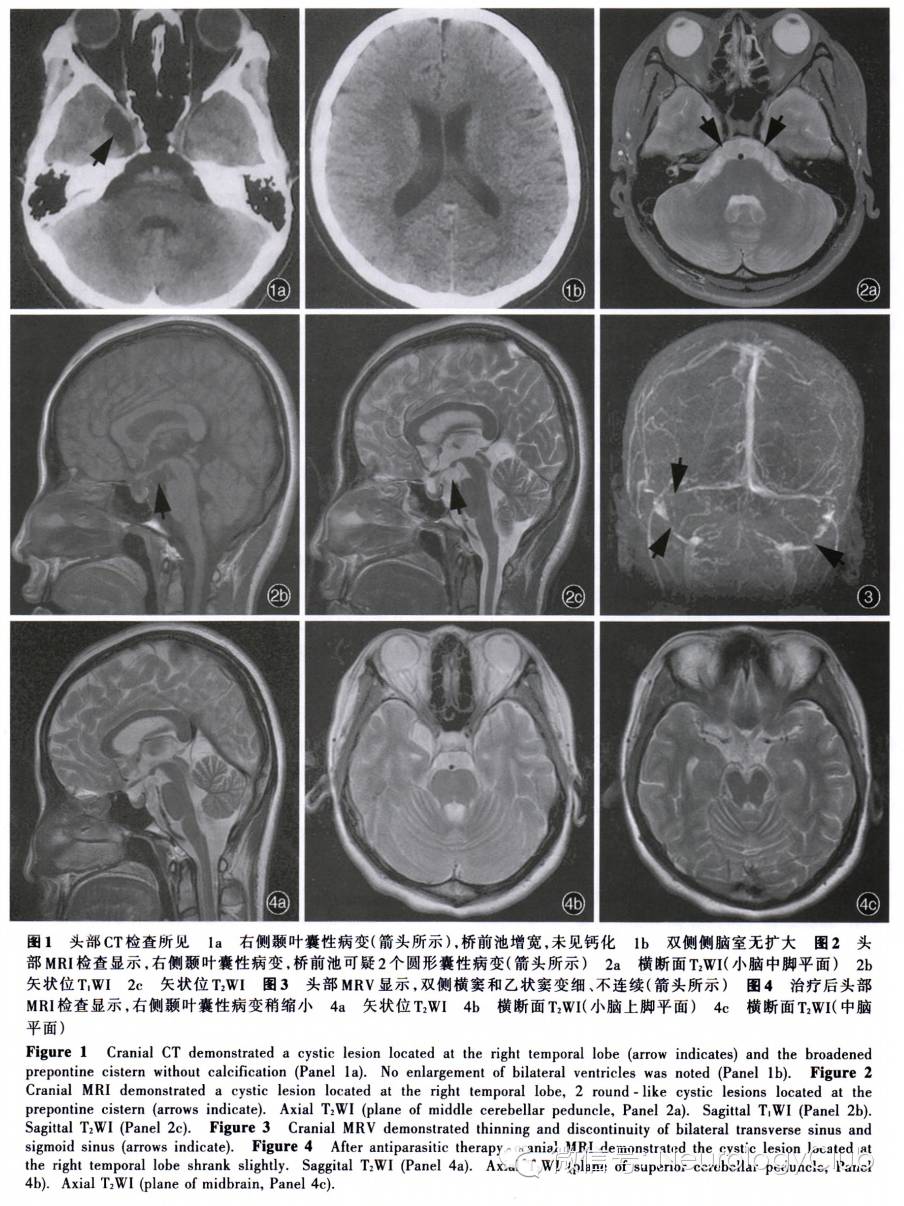

患者女性,19岁。主因左眼前黑影8个月,头痛1个月,视物模糊、耳鸣2周,于2015年1月30日入院。患者入院前8个月无明显诱因突发左眼前黑影,无头痛、视物模糊、眼红或眼痛,至当地医院眼科就诊。眼底镜检查显示,双眼视乳头水肿,左眼视乳头上方出血。视觉诱发电位(VEP)显示,双眼P100波潜伏期延长。头部CT显示,右侧颞叶蛛网膜囊肿,未见脑室扩大(图1)。诊断为眼底出血,口服活血药(具体方案不详)3d后左眼前黑影消失。1个月前无明显诱因出现头痛,全头部或偏侧(左右侧不明)持续性疼痛,难以忍受,稍恶心,呕吐少量胃内容物2次,无发热、畏光畏声,视觉模拟评分(VAS)7-8分;次日至当地医院就诊,予以天麻和甘露醇(具体剂量不详)静脉滴注,1周后头痛症状明显好转,遗留头部沉重感,无走路不稳、视物旋转。3周前再次出现左眼前黑影,自行口服活血药,黑影范围缩小但不消失;2周前稍感双眼视物模糊、单眼视物清晰,右侧似有耳呜,无听力下降,当地医院耳鼻咽喉科诊断为神经性耳鸣。眼科复查眼底镜仍显示双侧视乳头水肿。眼底荧光血管造影(FFA)显示双眼视盘充盈迟缓,晚期视盘高荧光,右眼动静脉充盈时间尚可,出血灶始终荧光遮蔽。头部MRI显示,右侧颞叶囊肿。为求进一步诊断与治疗遂至我院。眼科门诊查体右眼视力0.8、左眼0.6,眼压正常,眼前节未见异常;眼底镜显示,双眼视乳头边界模糊、隆起,视乳头表面毛细血管扩张,视网膜静脉轻度扩张。神经科门诊查体未见明显异常,以“视乳头水肿待查”收入院。2-4d前出现下腹部隐痛,1d前出现畏寒、发热(体温最高38℃),无咽痛、流涕、咳嗽、咳痰,无尿频、尿急、血尿,无腹泻。患者自发病以来,精神、食欲、睡眠可,大小便正常,体重无明显变化,无明显口干、眼干、光过敏、雷诺现象、关节疼痛、口腔和外阴溃疡等免疫系统疾病表现。

诊断与治疗经过  入院后完善各项相关检查。实验室检查血清钾3.20mmol/L(3.50-5.50mmol/L)。血尿便常规、肝肾功能试验、血清电解质、凝血功能、感染四项[乙型肝炎病毒表面抗原(HbsAg)、丙型肝炎病毒抗体(HCV-Ah)、梅毒螺旋体(TP)抗体、人类免疫缺陷病毒(HIV)抗体]均阴性。炎性指标红细胞沉降率(ESR)、超敏C-反应蛋白(hs-CRP)、免疫球蛋白、补体均正常;EB病毒IgM,TORCH(10项,包括弓形虫、风疹病毒、巨细胞病毒、I型和II型单纯疱疹病毒)IgM和IgG,以及结核杆菌感染T细胞斑点试验(T-SPOT.TB)均呈阴性;甲状腺功能试验、血浆皮质醇和促肾上腺皮质激素(ACTH)均于正常值范围。腰椎穿刺脑脊液检查压力>330mmH2O(1mmH2O=9.81×10^-3kPa,70-180mmH2O),细胞总数为252×10^6/L,白细胞计数为116×10^6/L[(0-8)×10^6/L],单个核细胞(包括单核细胞、淋巴细胞)比例98%,多个核细胞(包括中性粒细胞、嗜酸性粒细胞等)比例2%,脑脊液细胞学提示以淋巴细胞为主的炎症反应,伴嗜酸性粒细胞比例增加(5%);蛋白定量0.61g/L(0.15-0.45g/L),葡萄糖1.90mmol/L(2.80-4.50mmol/L),氯化物水平正常;寡克隆区带(OB)阳性,抗酸染色、墨汁染色、隐球菌抗原、TORCH(10项)IgM和IgG均呈阴性。心电图可见各导联U波,余未见异常。腹部B超未见明显异常,子宫双附件B超显示子宫内膜增厚。胸部X线显示心肺膈未见明显异常。头部MRI显示,右侧颞叶囊性病变,桥前池可疑囊性病变,增强扫描脑实质和脑膜未见明显强化(图2)。MRV显示双侧横窦和乙状窦变细、不连续(图3)。根据患者脑脊液嗜酸性粒细胞比例增加、桥前池可疑囊样病变,完善相关检查:粪便未检出寄生虫及其幼虫;血清和脑脊液标本送检首都医科大学附属北京友谊医院显示囊虫IgG阳性;双侧胫腓骨x线显示左侧胫骨上段和右侧距骨片状高密度影,提示骨岛形成,余未见明显异常。根据患者搏动性耳鸣,完善相关检查:经颅多普勒超声(TCD)显示右侧大脑中动脉血流速度增快,闻及杂音,提示狭窄可能,各血流频谱阻力指数增加,支持颅内高压;MRA未见明显异常。临床诊断为脑囊虫病。予阿苯达唑0.40g(2次/d)口服3周、甘露醇静脉滴注降低颅内压、地塞米松5mg(2次/d)静脉滴注抗感染,耳鸣症状逐渐消失,视物不清好转,血常规、肝肾功能试验基本正常;复查眼底镜仍显示双侧视乳头水肿;眼部B超显示双眼视盘隆起,程度较前减轻;TCD显示各血流频谱阻力指数较前明显下降,右侧大脑中动脉血流速度增快,可能存在轻度狭窄;MRI显示右侧颞叶囊性病变较前略缩小,桥前池无明显变化(图4)。阿苯达唑治疗第3周时开始缓慢减少激素剂量,减量第2天即出现畏寒、发热、耳呜,无咽痛、咳嗽症状与体征,完善血常规、血液培养、红细胞沉降率、超敏C-反应蛋白、胸部x线等相关检查未见明确中枢神经系统外感染证据,复查脑脊液压力>330mmH2O,细胞总数264×10^6/L,白细胞计数170×10^6/L,单个核细胞(包括单核细胞、淋巴细胞)比例71%,多个核细胞(包括中性粒细胞、嗜酸性粒细胞等)比例29%,脑脊液细胞学提示以中性粒细胞为主的炎症反应,嗜酸性粒细胞比例较前稍下降(3%);蛋白定量0.41g/L、葡萄糖2mmol/L、氯化物正常。考虑为驱虫治疗所致炎症反应可能性大,地塞米松恢复至5mg(2次/d)静脉滴注,同时加用头孢曲松钠(罗氏芬)1g(2次/d)静脉滴注抗感染治疗,患者发热、耳鸣症状缓解。住院39d,出院后间隔1个月,于当地医院按照原方案进行驱虫治疗。建议3-4个疗程后复查血清和脑脊液囊虫抗体,以及头部MRI。

放射科医师  脑囊虫病根据囊尾蚴部位可以分为脑实质型、脑室型、蛛网膜下隙型和脊髓型,其中,蛛网膜下隙型者囊虫位于颅底和外侧裂时体积较大,活虫无钙化,周围水肿和强化效应均不明显,囊内偏中央部位偶见T1WI等信号,为虫体头节,具有诊断价值。该例患者CT未见钙化,MRI显示桥前池类圆形囊性病变,囊内偏中央部位可见T1WI等信号,可能为虫体头节,但右侧颞叶囊性病变形状欠规则,体积较大,未见虫体头节,不能确定为囊虫。抗寄生虫治疗后病灶体积缩小,支持脑囊虫病诊断。

该例患者为青年女性,出生并长期居住在黑龙江省;临床主要表现为颅内高压症状,无癫痫发作,除眼动欠充分外,无其他局灶性神经系统症状;头部CT未见钙化灶,MRI显示右侧颞叶囊性病变;予抗寄生虫和降低颅内压治疗后病灶缩小,提示囊虫感染。桥前池可疑圆形囊性病变,囊内可见偏心点状信号,可疑含头节的囊尾蚴;血清和脑脊液囊虫抗体阳性,故脑囊虫病诊断明确,根据受累部分,进一步分为蛛网膜下隙型。值得注意的是,该例患者发病隐匿,慢性病程,临床以眼底出血为首发症状,眼底镜显示双侧视乳头水肿,未行进一步诊断与治疗,此后出现视物模糊、耳鸣、短暂性头痛,伴轻度恶心、呕吐,头部CT和MRI显示右侧颞叶囊性病变,边缘清晰,周围无水肿。初期考虑蛛网膜囊肿,蝶鞍周围和桥前池结构稍显紊乱但不明显,延迟了明确诊断时间,进一步加深了脑囊虫病可以模拟任何表现的临床印象。因此,熟悉脑囊虫病神经影像学特点、合理应用免疫学方法,对未发现明确病因的颅内高压,尤其是来自流行地区的患者,应警惕脑囊虫病,避免误诊和漏诊。